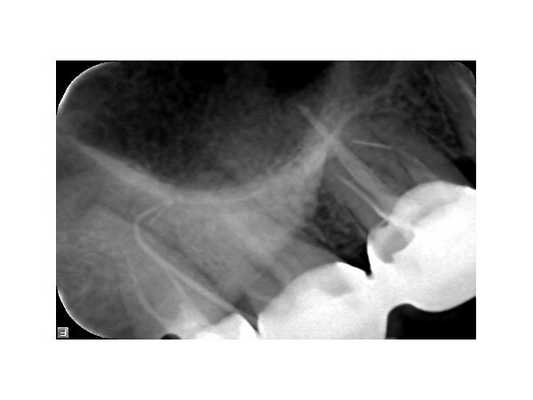

В поликлинике "Наша Клиника-Дент" проведено визиографическое обследование свищевого хода, предварительно в него был введён гуттаперчевый штифт для уточнения локализации воспалительного процесса. Выявлен очаг воспаления в области корней 17 зуба. Также обнаружен участок повышенной плотности, по конфигурации соответствующий фрагменту инструмента в мезиально-щёчном корне 16 зуба.

После снятия коронки и старой пломбы. Видно кариес, который мог быть дополнительным источником инфекции.